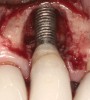

Some amount of microleakage can be expected with any current implant-abutment interface.23,24 External hexagon implants have been found to fail to prevent microleakage.23 Figure 3 and Figure 4 depict an external hexagon implant with an implant-abutment connection vulnerable to microleakage. This same study found internal hexagon implants with internal conical (Morse taper) connection to have the least amount of leakage. Zirconia abutments were found to have more microleakage than titanium abutments. As a result, this study recommended restricting the use of zirconia abutments to cases where esthetic demands are high.23

Fig 3. Clinical and radiographic views of an external hexagon implant restored using a zirconia abutment. The radiograph indicates an implant–abutment connection vulnerable to microleakage. Severe bone loss was due to peri-implantitis.

Figure 3

Fig 4. Clinical and radiographic views of an external hexagon implant restored using a zirconia abutment. The radiograph indicates an implant–abutment connection vulnerable to microleakage. Severe bone loss was due to peri-implantitis.

Figure 4